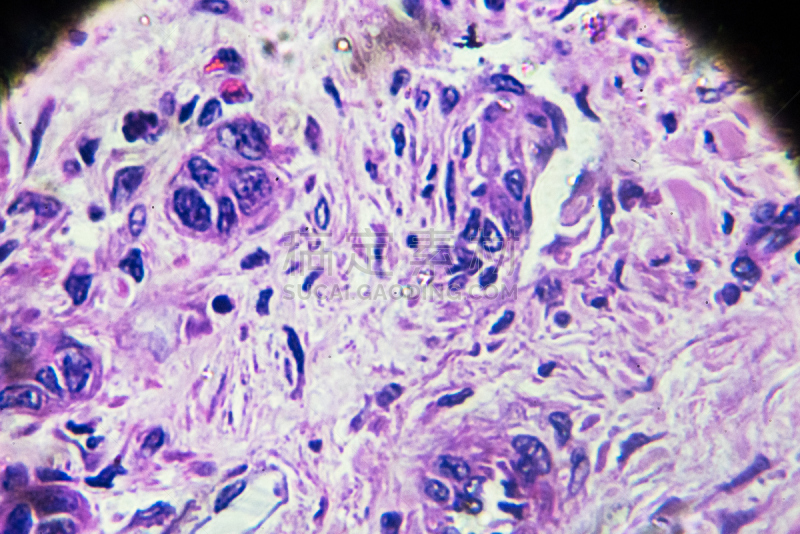

人类的肝脏解剖学详情

JPG